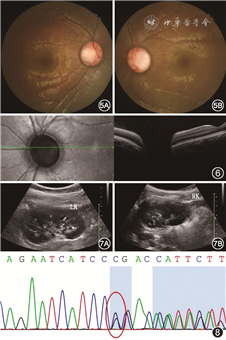

其母未见明显眼部异常,父亲视力为右眼20 cm手动,矫正不提高,左眼0.4矫正至0.8,前节无明显异常,散瞳查眼底可见右眼视盘增大,血管走行异常,盘周可见环形萎缩弧;左眼视盘大小正常,视网膜血管数目增多,自盘周放射状发出,可见视盘鼻侧有髓神经纤维及黄斑区视网膜劈裂(图3)。OCT同样可见视杯深而宽,左眼黄斑区及盘周视网膜劈裂,右眼黄斑区视网膜神经上皮浅脱离(图4)。先证者妹妹双眼矫正视力为0.2,眼前节未见明显异常,散瞳查眼底可见双眼视盘大小、血管数量及走行大致正常,视杯宽而深,颞侧盘沿窄(图5)。OCT可见宽而深的视杯,黄斑区未见明显异常(图6)。

肾脏B超示先证者及其妹妹双侧肾脏钙化灶及肾盂分离(图7),患者父亲移植肾未见明显异常。先证者及其妹妹尿常规示轻度蛋白尿。采用目标区域捕获+高通量测序对先证者及其父亲、母亲、妹妹进行基因检测,在先证者及其父亲、妹妹PAX2基因外显子区域发现一处杂合突变:c.419_421delGGA(缺失突变),突变导致氨基酸改变p.R140_T141delinsP(缺失-插入突变)(图8),PAX2基因与局灶性节段性肾小球硬化症7型、肾-视神经乳头缺损综合征相关,为常染色体显性遗传。结合基因检测结果以及特征性的眼部、肾脏改变,可确诊患儿及其父亲、妹妹为肾-视神经乳头缺损综合征。